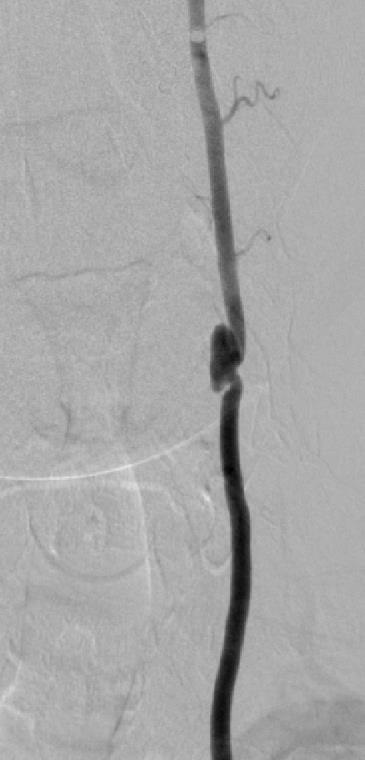

末端动脉阻塞(end-artery occlusion)

末端动脉栓塞:医源性肾损伤-移植肾活检

活检后动脉瘤破裂 |

微导管在载瘤动脉末端 |

载瘤动脉末端栓塞 |

Coil=3 |